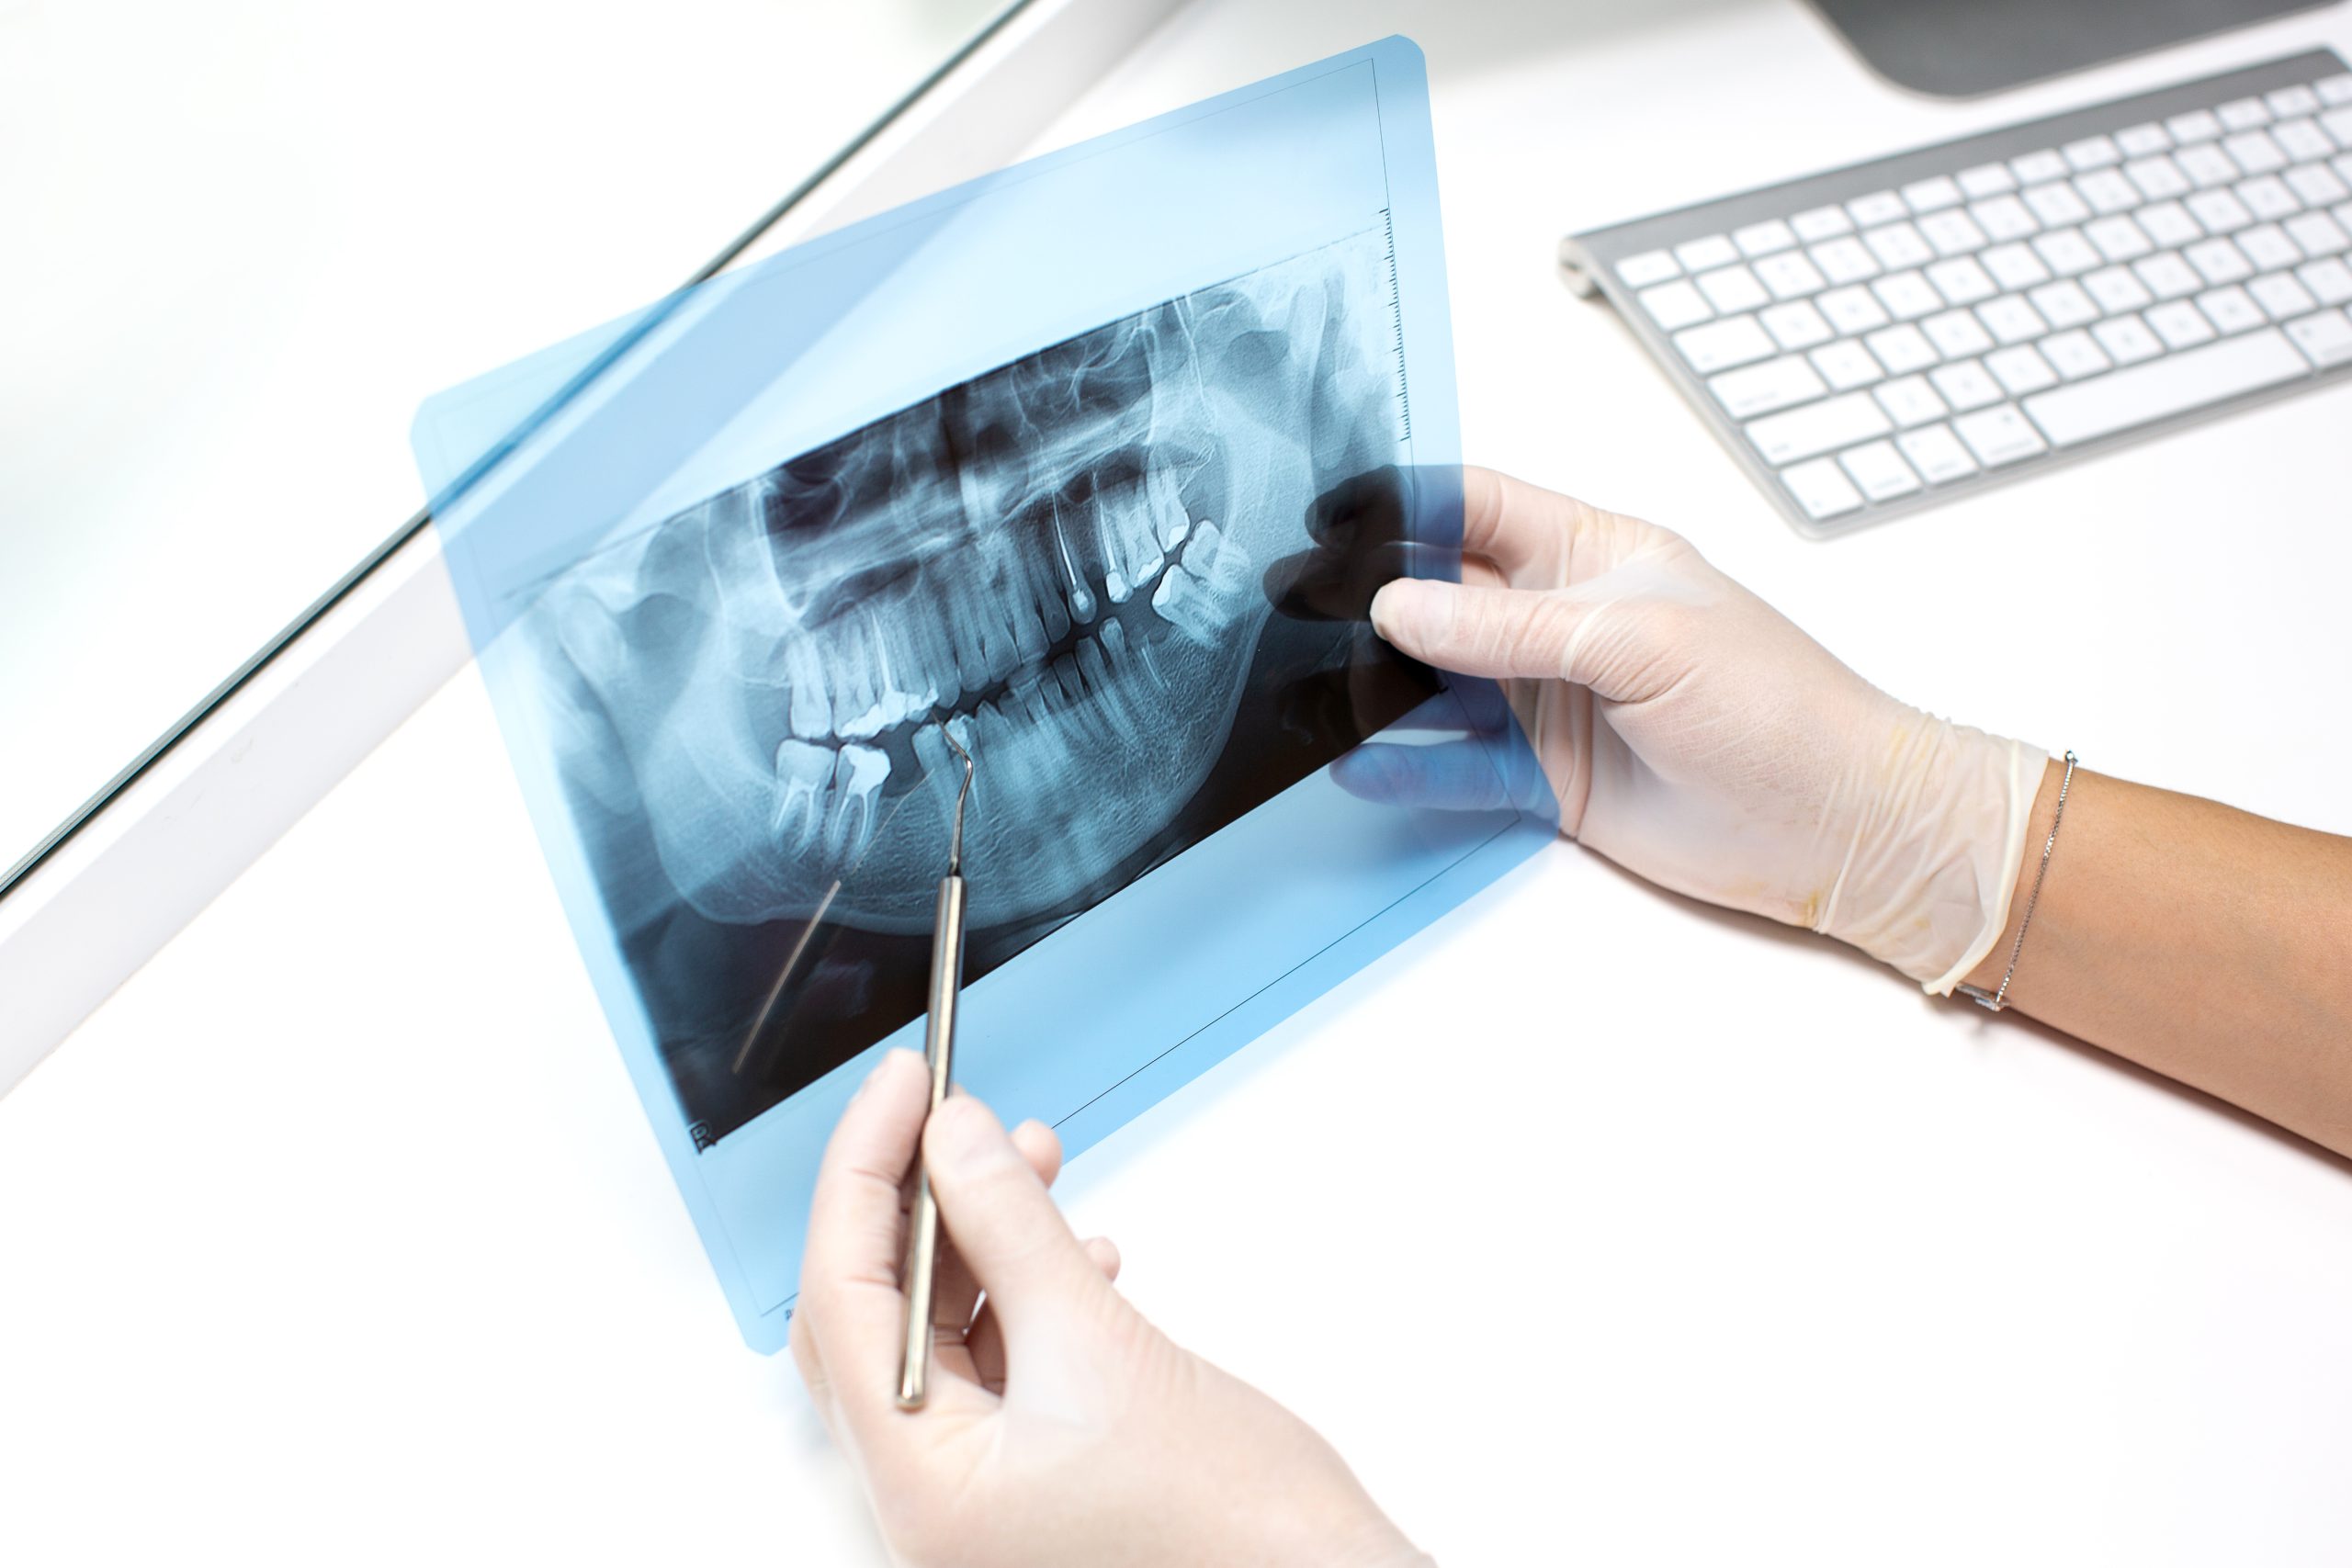

Diagnóstico con tecnología digital

Utilizamos radiografías digitales y pruebas de vitalidad pulpar para evaluar el estado del nervio dental y planificar el tratamiento con exactitud.